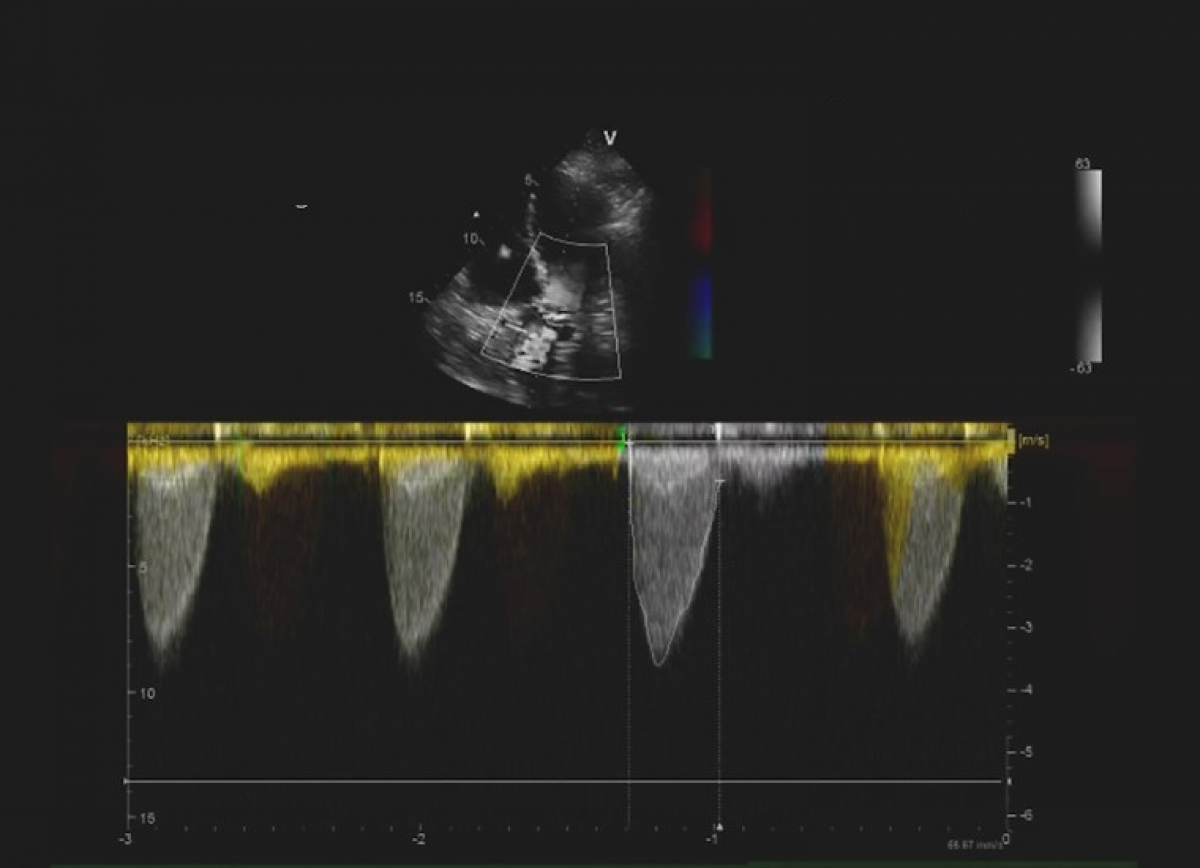

Pacjentka z niewydolnością serca NYHA II, po leczeniu operacyjnym wady mitralnej, z utrwalonym migotaniem przedsionków.

Ciężka (masywna) wtórna niedomykalność trójdzielna. Stan po plastyce zastawki mitralnej.

Ocena niedomykalności trójdzielnej.